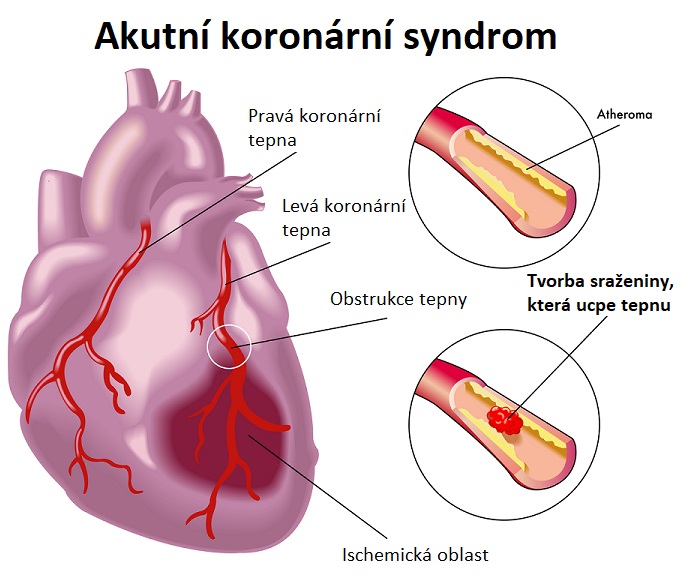

BRATISLAVA – Slovensko čelí znepokojivému trendu v oblasti kardiovaskulárneho zdravia. Najnovšie štatistiky Národného centra zdravotníckych informácií (NCZI) ukazujú prudký nárast hospitalizácií pre akútny koronárny syndróm (AKS). Hoci počet prípadov rastie naprieč pohlaviami aj vekovými skupinami, odborníci poukazujú aj na pozitívny vývoj – úmrtnosť pacientov dlhodobo klesá.

Symptómy AKS Bolesť na hrudníku, ktorá môže vyžarovať do horných končatín a krku Bolesť medzi lopatkami, alebo v nadbrušku Spotenie, zvracanie, pocit na odpadnutie, bezvedomie

Odborníci upozorňujú, že okrem veku a genetickej predispozície zohráva zásadnú úlohu aj životný štýl – fajčenie, obezita, nedostatok pohybu či neliečená hypertenzia výrazne zvyšujú riziko srdcového infarktu.

Lekári varujú pred nebezpečným čakaním

Kardiológovia zároveň apelujú na verejnosť, aby nepodceňovala varovné príznaky. „Stále sa stretávame s pacientmi, ktorí majú bolesti na hrudníku, no niekoľko dní vyčkávajú. To môže mať fatálne následky,“ upozorňuje MUDr. Hovanjec.

Ak bolesť na hrudi trvá viac než 10 až 15 minút, zhoršuje sa pri námahe alebo ju sprevádzajú ďalšie príznaky, je podľa odborníkov nevyhnutné okamžite vyhľadať lekársku pomoc.